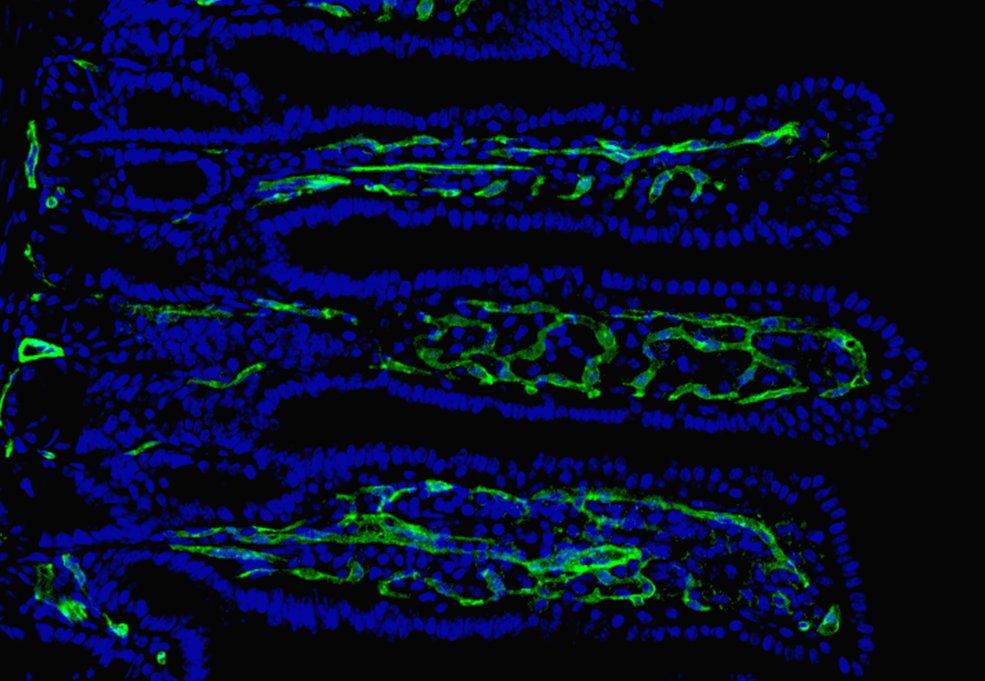

Die Forschenden stellten fest, dass die Interaktion der Bakterien mit der Darmbarriere einen Mechanismus auslöst, durch den das Protein Neuropilin-1 im Darmepithel abgebaut wird. Ohne dieses wichtige Protein sinkt die Aktivität des Hedgehog-Signalwegs. Dies führt dazu, dass die Zellentwicklung gestört ist und weniger stabilisierende Bestandteile im Darmepithel gebildet werden. Die Folge: eine geschwächte und durchlässige Darmbarriere.

Darüber hinaus entdeckte das Forschungsteam, dass ein Mangel an Neuropilin-1 die Bildung von Gefäßen in den Darmzotten beeinträchtigt. Diese Kapillargefäße sind besonders wichtig, um Nährstoffe effektiv aufnehmen zu können.